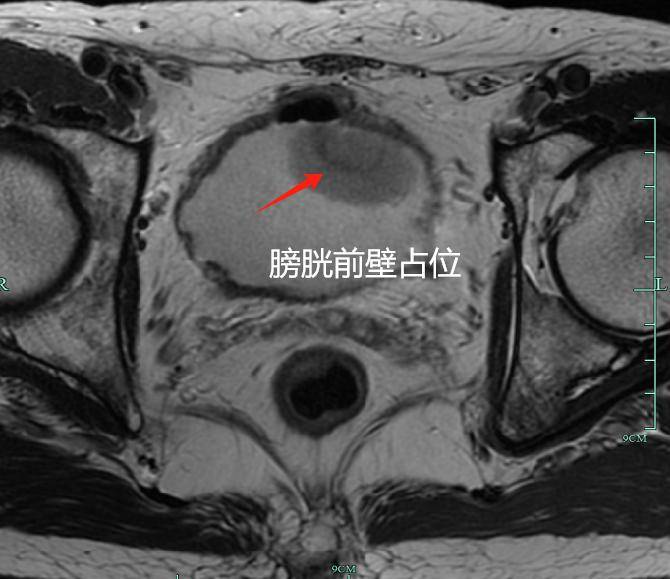

浙江温州50岁的亮哥(化名) 正坠入人生的至暗时刻 膀胱恶性肿瘤的诊断 像块巨石砸懵了他 而更残酷的现实摆在眼前: 为阻止肿瘤复发 医生很可能切除他的膀胱、前列腺 这意味着余生或将与尿袋为伴 正常排尿